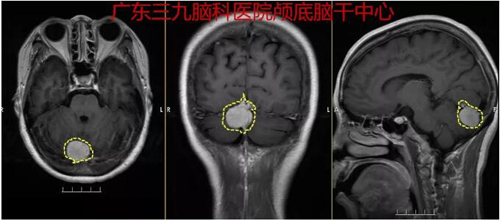

图2:术前MR示右侧枕部小脑幕下示一类圆形占位性病变,呈稍长T1长T2异常信号影,FLAIR序列呈稍高信号影,增强后病变明显均匀强化,范围约为2.5cm×2.0cm×1.7cm。双侧大脑半球皮层下白质内、双侧侧脑室周围及双侧半卵圆中心示多发点状等、稍长T1长T2异常信号影,FLAIR序列呈高信号